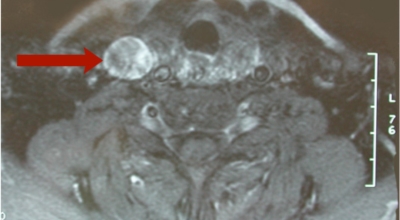

갑상성암진단

초음파검사, 세침흡입 검사, 동위원소검사 등이 있답니다. 초음파검사는 간편하고 혹의 크기, 모양, 갯수등을 확인하는데 도움을 줘요. 암인지 아닌지 확인하기 위하여는 세침 흡인 세포검사가 가장 유용하게 활용돼요. 갑상선 초음파 검사에서 갑상선의 결절을 검사해요.

결절이 발견되면 석회화 여부, 폭과 길이의 비율, 결절의 경계와 크기 등을 석회화하여 암 여부를 확인해요. 일단 결절이 석회화되면 암일 가능성이 높고, 경계가 불분명하고 방사상으로 뻗어나갈 때 암일 가능성이 높아요.

또한 악성 결절(암)의 경우 평균적으로 세로 길이가 조금 더 긴 것으로 관찰돼요. 또한 결절의 종류에 따라 시술이 구분되어요.첫째, 침술(FNA)과 조직검사를 통해 결절이 양성이면 결절을 따라갑니다. 결절이 사라지지 않으면 초음파와 FNA를 통해 다시금 검사해요. 조직검사에서 악성이 발견되면 없애주는 수술을 해요. 조직 검사에서 불분명한 결과가 나타나면 갑상선 스캔이 활용돼요.